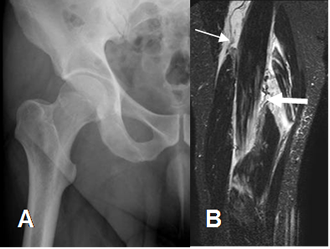

Fig 24. Ruptura muscular.

A: Rx AP. Estudio normal. No se identifican avulsiones.

B: RM coronal en STIR. Rupturas retraídas en los músculos semimembranoso (Flecha gruesa) y bíceps femoral. (Flecha delgada).